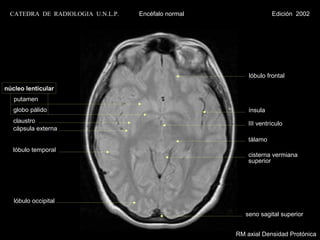

lóbulo frontal

núcleo lenticular

putamen

globo pálido                                         ínsula

claustro                                             III ventrículo

cápsula externa

tálamo

lóbulo temporal

cisterna vermiana

superior

lóbulo occipital

seno sagital superior

RM axial Densidad Protónica